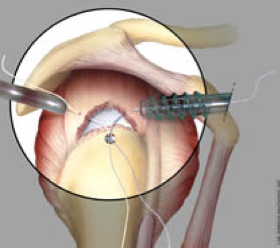

L’obiettivo dell’intervento di riparazione è di riportare il lembo di tendine strappato alla sua sede di inserzione all’osso della testa omerale e fissarvelo. Per far questo esistono diversi sistemi di ancoraggio, i più comuni sono rappresentati da “ancorette” di vari materiali che si avvitano o si impiantano a pressione nell’osso e a cui sono attaccati dei fili con i quali si sutura e si riporta in sede il tendine (fig. 6, 7, 8). I dispositivi utilizzati sono i più innovativi, e quando possibile utilizziamo ancorette di solo filo, riassorbibili o radiotrasparenti in modo da ridurre ulteriormente l’invasività chirurgica.